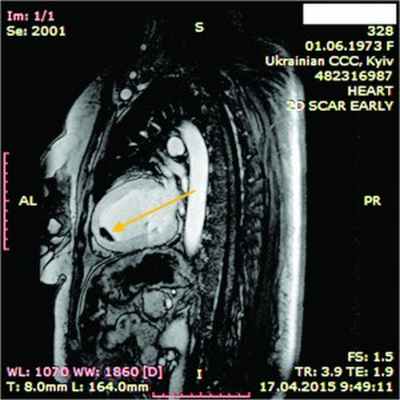

При рентгенологическом обследовании органов грудной клетки обнаруживают кардиомегалию и признаки венозного застоя в легких. Изменения ЭКГ не специфичны. Частые находки – нарушения ритма сердца, особенно фибрилляция предсердий (ФП). В диагностике заболевания основную роль играет эхокардиография (ЭхоКГ), позволяющая обнаружить локальное (реже – диффузное) утолщение верхушки одного или обоих желудочков с вовлечением в патологический процесс хорд, умеренную митральную или трикуспидальную регургитацию, пристеночные, особенно верхушечный, крупные тромбы. Показательным является «рестриктивный тип» ремоделирования сердца и внутрисердечной гемодинамики – очевидное преобладание объема предсердий над объемами желудочков. Систолическая функция, как правило, сохранена, но диагностируется диастолическая дисфункция – рестриктивный тип трансмитрального/транстрикуспидального кровотока. Наиболее информативными методами исследования на сегодняшний день являются магнитно-резонансная томография (МРТ) и мультиспектральная компьютерная томография с контрастированием 14. В литературе описан случай динамического наблюдения за развитием эндокардита Леффлера с серией одновременно производимой позитронно-эмиссионной томографии и контрастированной МРТ с выделением стадий: бессимптомной, острой некротической, симптомной тромботической и фибротической [13]. Выполнение эндомиокардиальной биопсии миокарда правого (ПЖ) или левого (ЛЖ) желудочка позволяет подтвердить или опровергнуть диагноз эндокардита Леффлера.

14.04.2015 г. пациентка была госпитализирована в Национальный научный центр «Институт кардиологии им. Н.Д. Стражеско» в отделение некоронарогенных заболеваний сердца и клинической ревматологии, где был выставлен (подтвержден и уточнен) диагноз: ГЭС. Эндокардит Леффлера с поражением ЛЖ и ПЖ. Массивные пристеночные тромботические наслоения в ПЖ. Апикальный тромб ЛЖ. Мелкие тромбы в ушках обоих предсердий. Синусовая тахикардия. Единичные желудочковые ЭС. Перикардит с небольшим количеством жидкости. СН IIА ст. со сниженной сократительной функцией ЛЖ ІІ ФК по NYHA. Аутоиммунный тиреоидит, эутиреоз. Токсокароз, висцеральная фаза.

ЭхоКГ: Патологические изменения миокарда ПЖ с утолщением стенок до 18 мм. Диффузный гипокинез стенок ЛЖ с дискинезом верхушки – ФВ 44%. В области верхушки ПЖ – наслоения между листками перикарда. Небольшое количество жидкости в полости перикарда – по ЗСЛЖ до 5 мм. Таким образом, в динамике на ЭхоКГ наблюдалось снижение сократительной функции ЛЖ на фоне его гипертрофии и, несмотря на проведенную высокодозовую терапию гормонами, не уменьшилась гипертрофия ПЖ.

В ходе серии динамических МРТ с контрастированием (рис. 7-11) выявлены массивные пристеночные тромботические наслоения в ПЖ, апикальный тромб ЛЖ.